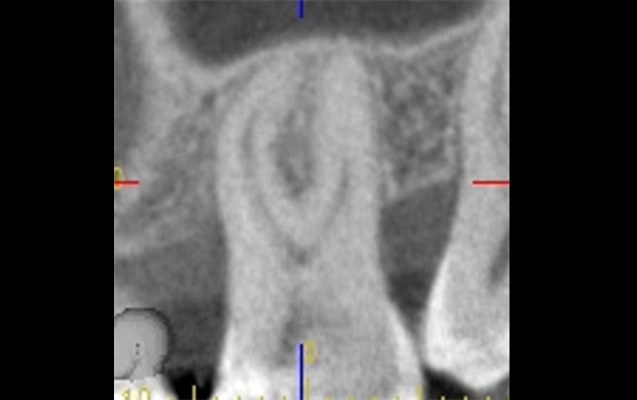

歯を長持ちさせるために必要なことは「歯の外に対しての歯周病治療、歯の中に対しての根管治療」です。両者が複雑に絡んでいるケースもあり、それぞれに対処が必要な場合もあります。そのような場合でも歯科用CT・マイクロスコープを活用することで対応することが可能です。

難易度の高い治療ではありますが、歯科用CTによる正確な診断、マイクロスコープを用いた精密な治療により可能となります。